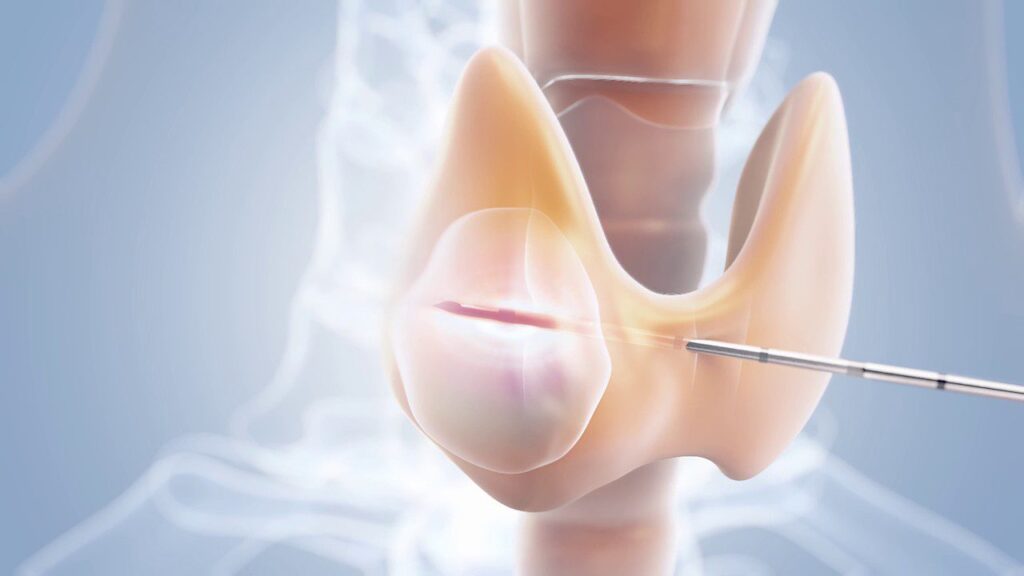

Kỹ thuật này sử dụng sóng cao tần để làm tăng nhiệt độ ở kim đốt làm huỷ nhu mô của bướu giáp. Sau khi gây tê tại vị trí chọc kim và gây tê bao giáp, theo dõi hình ảnh thông qua siêu âm, bác sĩ sẽ sử dụng loại kim chuyên dụng trong phương pháp RFA để tiếp cận với bướu giáp cần đốt. Tiếp theo, bác sĩ điều chỉnh cường độ đốt phù hợp để huỷ khối u.

Loại kim trong huỷ u đốt sóng cao tần có kích thước nhỏ (chỉ khoảng 1,3 mm) không gây đau cho người bệnh, hạn chế sẹo mổ

Khắc phục được những tồn tại trên trong điều trị bướu giáp, phương pháp hủy u bằng sóng cao tần sử dụng dòng điện tần số cao để giảm kích thước các nhân giáp lành tính mà ít xâm lấn, không có sẹo mổ, tăng tính thẩm mỹ.